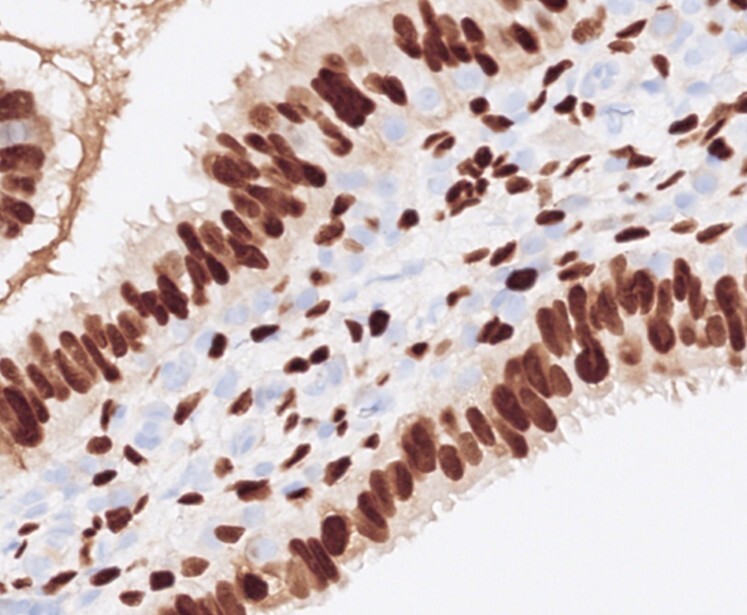

Histopathological examination (Figures 3 & 4) showed polypoid mucosal changes with papillary projections and cystic, dilated tubules lined by fallopian tube-type epithelium. No nuclear atypia, increased mitoses, or other Mullerian elements such as endocervical or endometrial tissue were identified. Immunohistochemistry (Figures 5-10) demonstrated positivity for CK7, oestrogen receptor, and progesterone receptor, while GATA3, P63, and CK20 were negative.

Radiological findings are often nonspecific, making pre-operative diagnosis challenging. Histological examination is essential for confirmation. It reveals tubal or papillary structures lined by characteristic fallopian tube-type epithelium with three types of cells, which include ciliated cells, mucinous cells, and intercalated cells, located in the lamina propria or muscularis propria of the urinary bladder wall. Immunohistochemistry findings are identical to the fallopian tube with CK7, oestrogen, and progesterone receptor positivity and absence of urothelial markers like GATA3, uroplakin II, uroplakin III and P63.